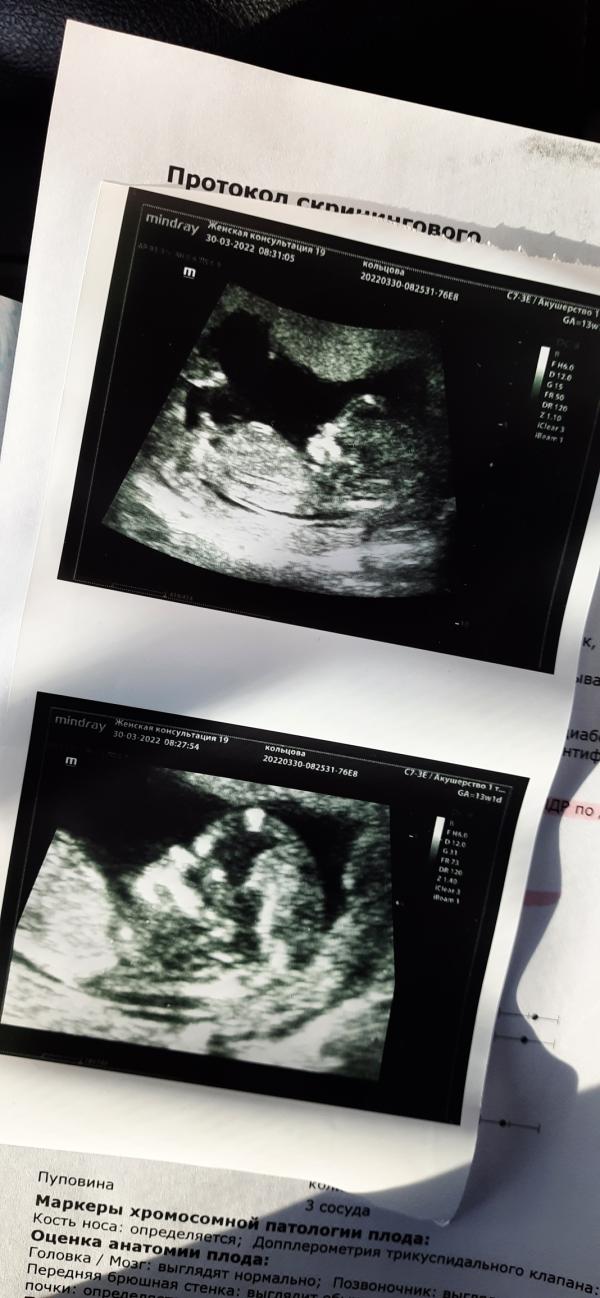

Первый скрининг😍

Здесь нам 13 недель)